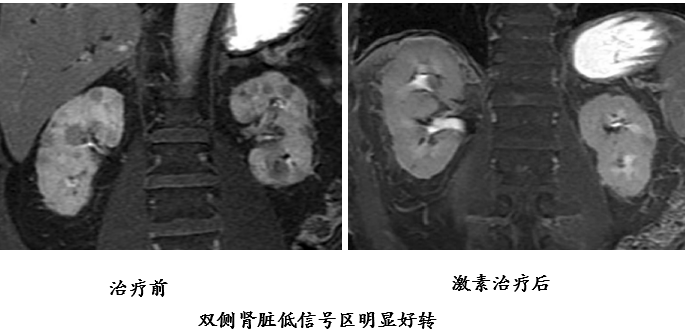

肾脏受累约见于 1/3 的 AIP 患者,为间质性肾炎。双肾多发病灶,CT 表现为皮质内小圆形、楔形、不规则形低密度灶,肾盂可受累,增强扫描动脉期呈低密度,延迟期呈轻度强化MRI:T1WI 等或低信号,T2WI 低信号,DWI 高信号,增强扫描轻度强化

肾脏受累治疗后

16b0ea80e77c28e2b64c663a5391501c.png